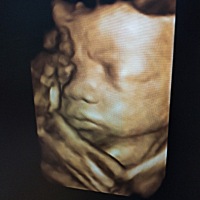

猜猜是女宝还是男宝